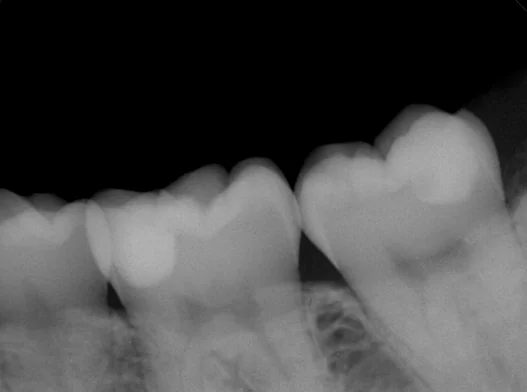

さて、写真だけだとどのくらいのサイズか非常にわかりづらい状態なので術後のレントゲンも今回は載せさせていただきます。

こんな感じで、左右ともに歯が1/3ほどない状態になっていました。

平面で見ると小さい虫歯っぽく見えますが、実際にはこれくらい進んでいたんですよね。